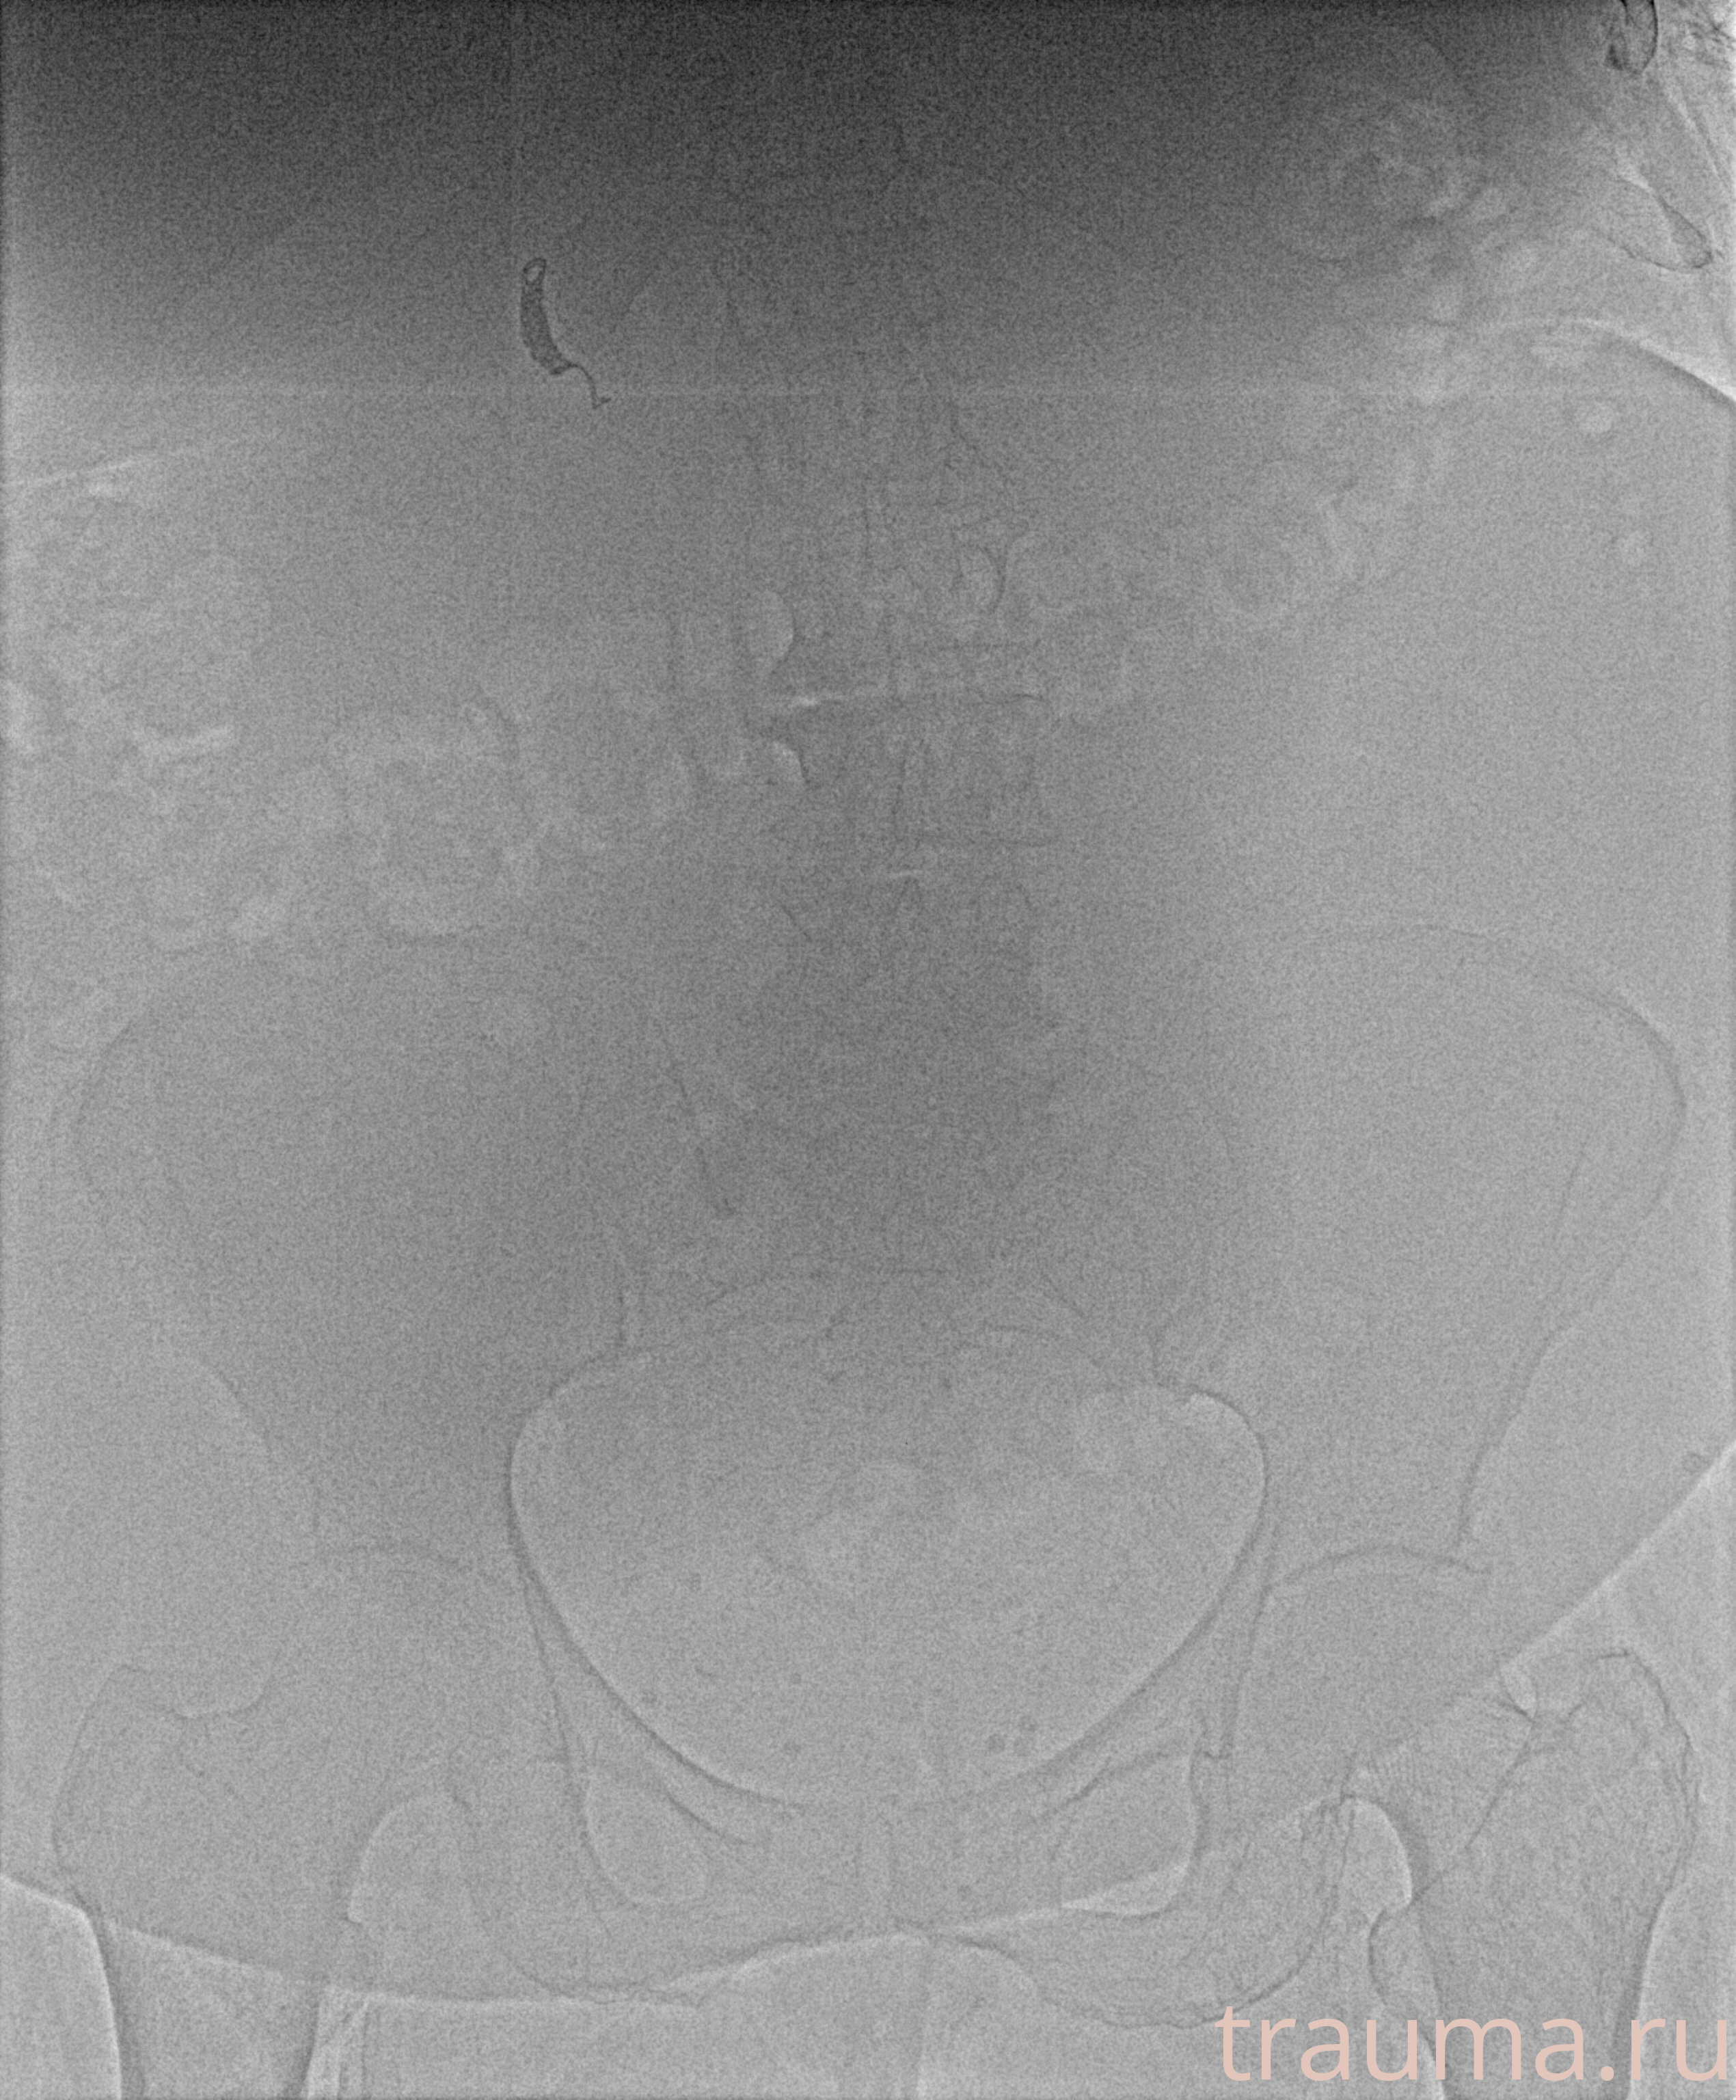

Рентгенограммы

Рентген на дому: по вашему адресу приезжает врач-рентгенолог, травматолог-ортопед с мобильным рентгеновским аппаратом, проводит диагностику травмы или заболевания, делает необходимые рентгенограммы, дает рекомендации по дальнейшему лечению. Получить качественные снимки в домашних условиях возможно благодаря уникальной методике, разработанной МосРентген Центром для института  Склифосовского